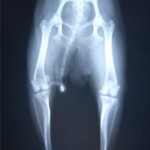

■ 症例24 キャバリア 7か月

左右膝蓋骨内方脱臼(左:グレードⅣ 右:グレードⅢ)

以前から左右後肢の跛行が認められ、整形外科学的検査・レントゲン検査により左右の膝蓋骨脱臼が認められた。症状が重度である左膝の膝蓋骨脱臼整復術を行った。外科手技は縫工筋及び内側広筋の解放、脛骨粗面の外側転位、滑車ブロック形造溝術、内外側関節方の縫縮を実施した。術後一か月時点で、左の膝蓋骨は安定しており経過は良好である。

■ 症例20 ポメラニアン 8ヶ月 1.8kg

左右膝蓋骨脱臼 グレードⅢ

2ヶ月前から間欠的跛行が認められ、両膝の膝蓋骨脱臼整復術を行った。